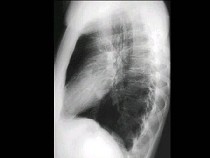

51、单项选择题

男,7岁,外伤后突发呼吸困难伴胸痛,结合图像,最可能的诊断是()

A.胸腔积液

B.肺大泡

C.气胸

D.液气胸

E.肺脓肿